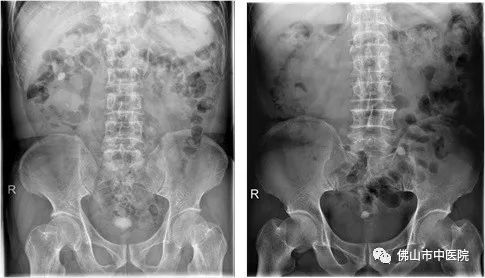

前列腺增生合并膀胱结石

尽管膀胱结石形成因素是综合性的,但是随着医疗条件的不断改善,一般通过常规的体检、根据临床表现、B超、X线检查等,膀胱结石大多还是能早期诊断、早期治疗,难以发展成膀胱巨大结石,目前常见的膀胱结石通常在3cm左右,该患者能形成如此巨大膀胱结石,实属罕见。